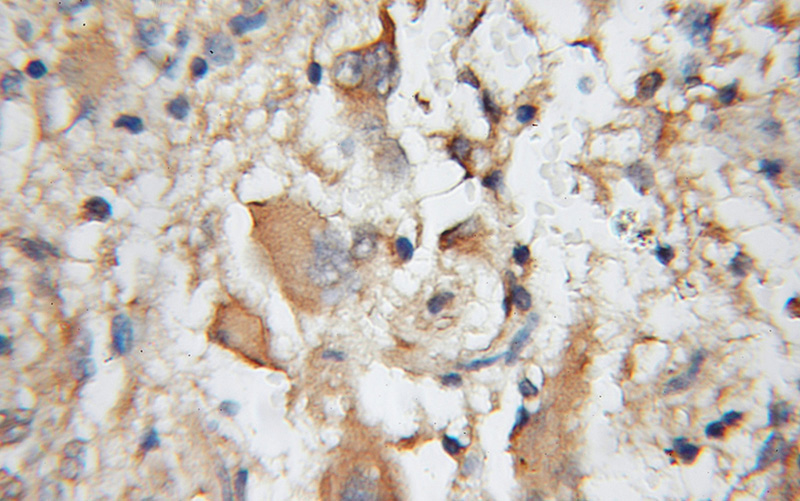

Immunohistochemical of paraffin-embedded human gliomas using Catalog No:108752(CA8 antibody) at dilution of 1:100 (under 10x lens)